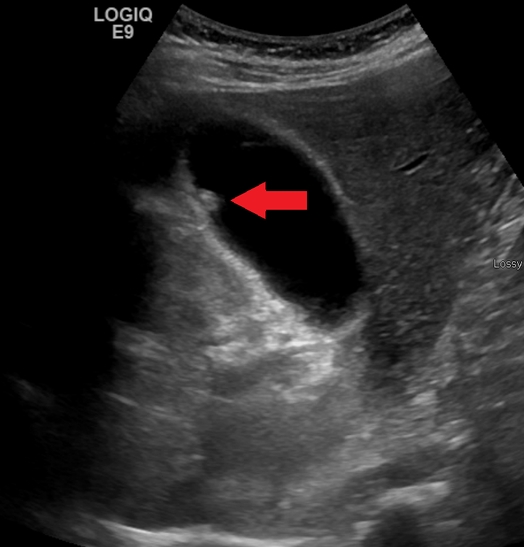

난소 낭종 파열에 대한 종합 가이드: 원인, 증상, 출혈, 종류 및 치료의 이해

난소 낭종 파열, 원인, 증상, 출혈, 유형 및 치료 옵션에 대해 알아보십시오. 이 상태를 효과적으로 관리하는 방법을 이해합니다. 난소 낭종에 대하여 “난소 낭종 파열”이라는 것에 대해 들어본 적이 있으신가요? 다소 복잡하게 들릴 수 있지만 걱정하지 마세요! 가능한 한 간단하게 설명해드리겠습니다. 이 글에서는 난소 낭종 파열의 원인, 증상, 출혈, 유형 및 치료 옵션에 대해 자세히 알아보겠습니다. … 더 읽기